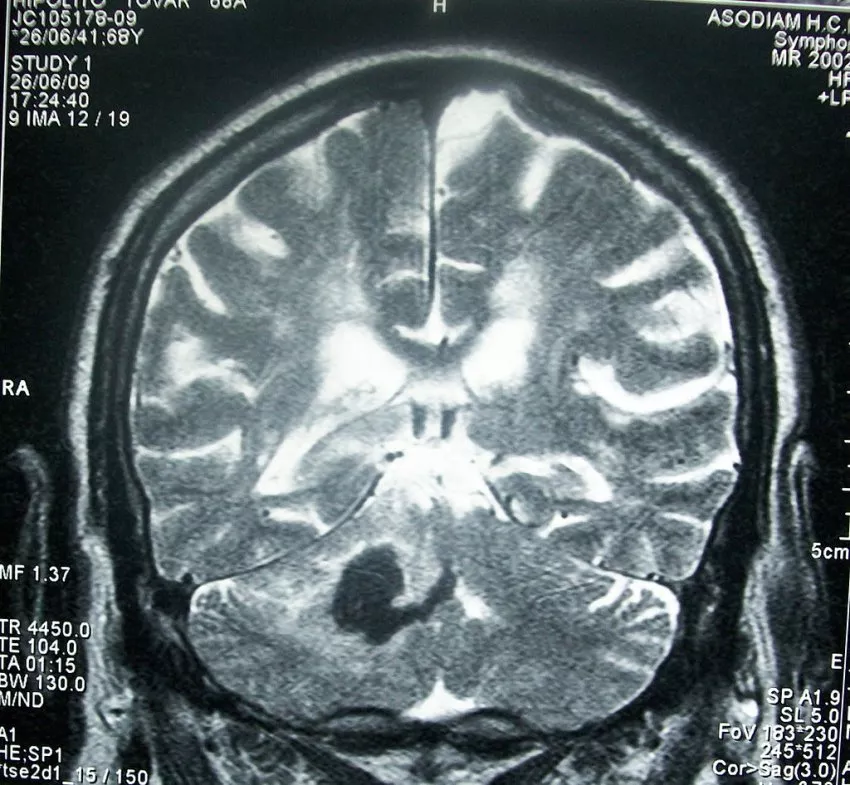

Stroke - Agyvérzés (30 órás, kisagy - cerebellum)

Forrás

Bobjgalindo; jogállás: CC-BY-SA-3.0 - Wikimedia Commons